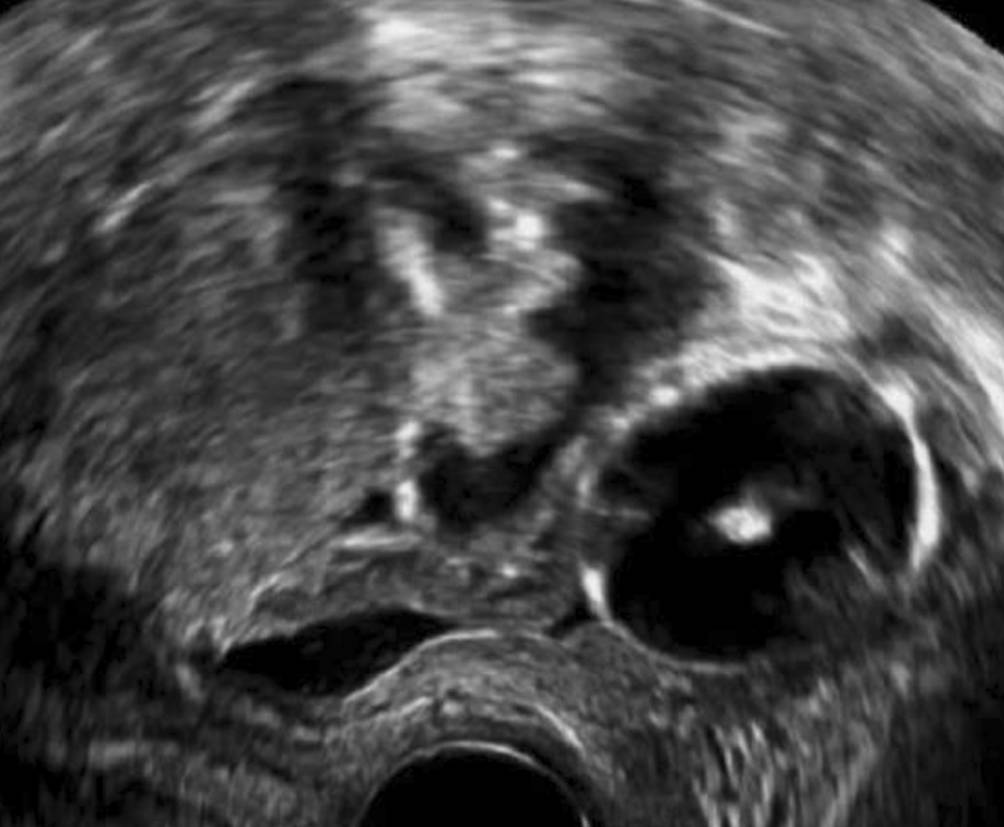

Abb. 6

Über Jahre konstante Gartner-Gang-Zyste, die trotz der unmittelbaren Nähe zur Blase der Patientin nie Beschwerden machte